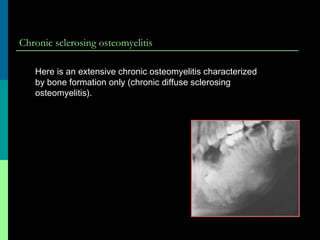

Chronic sclerosing osteomyelitis

Here is an extensive chronic osteomyelitis characterized

by bone formation only (chronic diffuse sclerosing

osteomyelitis).